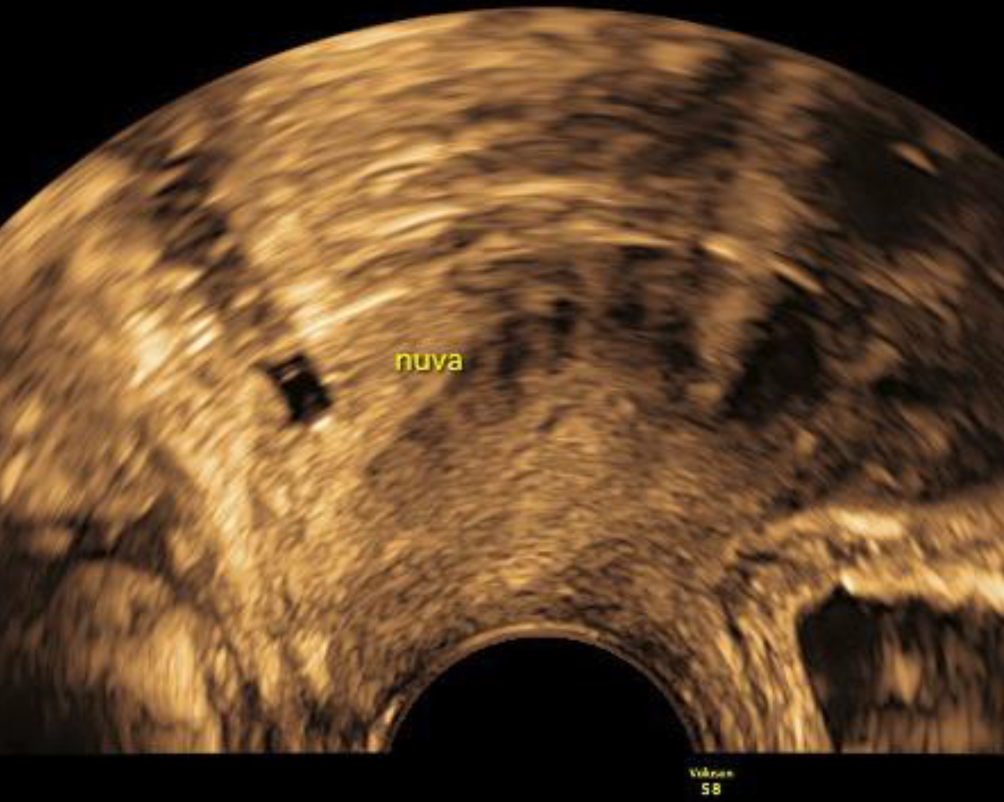

Abb. 7

Ein NuvaRing imponiert als rechteckiger, echoarmer Block unmittelbar hinter der Zervix und kann leicht mit Ovula Nabothi verwechselt werden. Er wirft einen charakteristischen distalen Schatten („shadowing“)